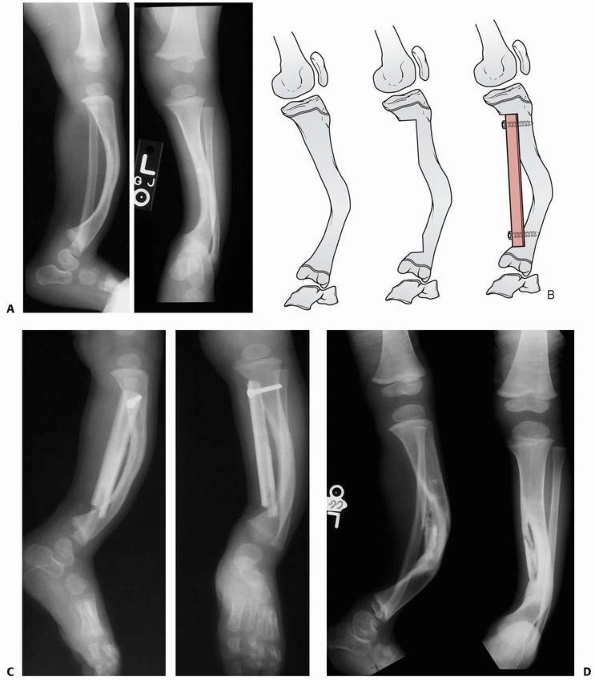

FIGURE 6-4 Classification system for the treatment of pathologic fractures of the proximal femur associated with bone cysts in children. A.

In type IA, a moderately sized cyst is present in the middle of the femoral neck. There is enough bone in the femoral neck and lateral proximal femur (lateral buttress) to allow fixation with cannulated screws, avoiding the physis, after curettage and bone grafting. B. In type IB, a large cyst is present at the base of the femoral neck. There is enough bone proximally in the femoral neck but there is loss of lateral buttress, so a pediatric hip screw and a side plate should be considered rather than cannulated screws after curettage and bone grafting. C,D. In type II A-B, a large lesion is present in the femoral neck, so there is not enough bone beneath the physis to accept screws. There are two options for treatment of these bone cysts: (i) after curettage and bone grafting, parallel smooth pins across the physis can be used in combination with spica cast; (ii) the patient can be treated in traction until the fracture heals (with subsequent spica cast) followed by curettage and bone grafting. E,F. In type IIIA-B, the physis is closing or closed. The lateral buttress is present in type IIIA hips, so cannulated screws can be used to stabilize the fracture after curettage and bone grafting. In type IIIB hips, the loss of lateral buttress makes it necessary to use a pediatric hip screw and a side plate following curettage and bone grafting. In all types, we recommend spica cast immobilization after surgery. |